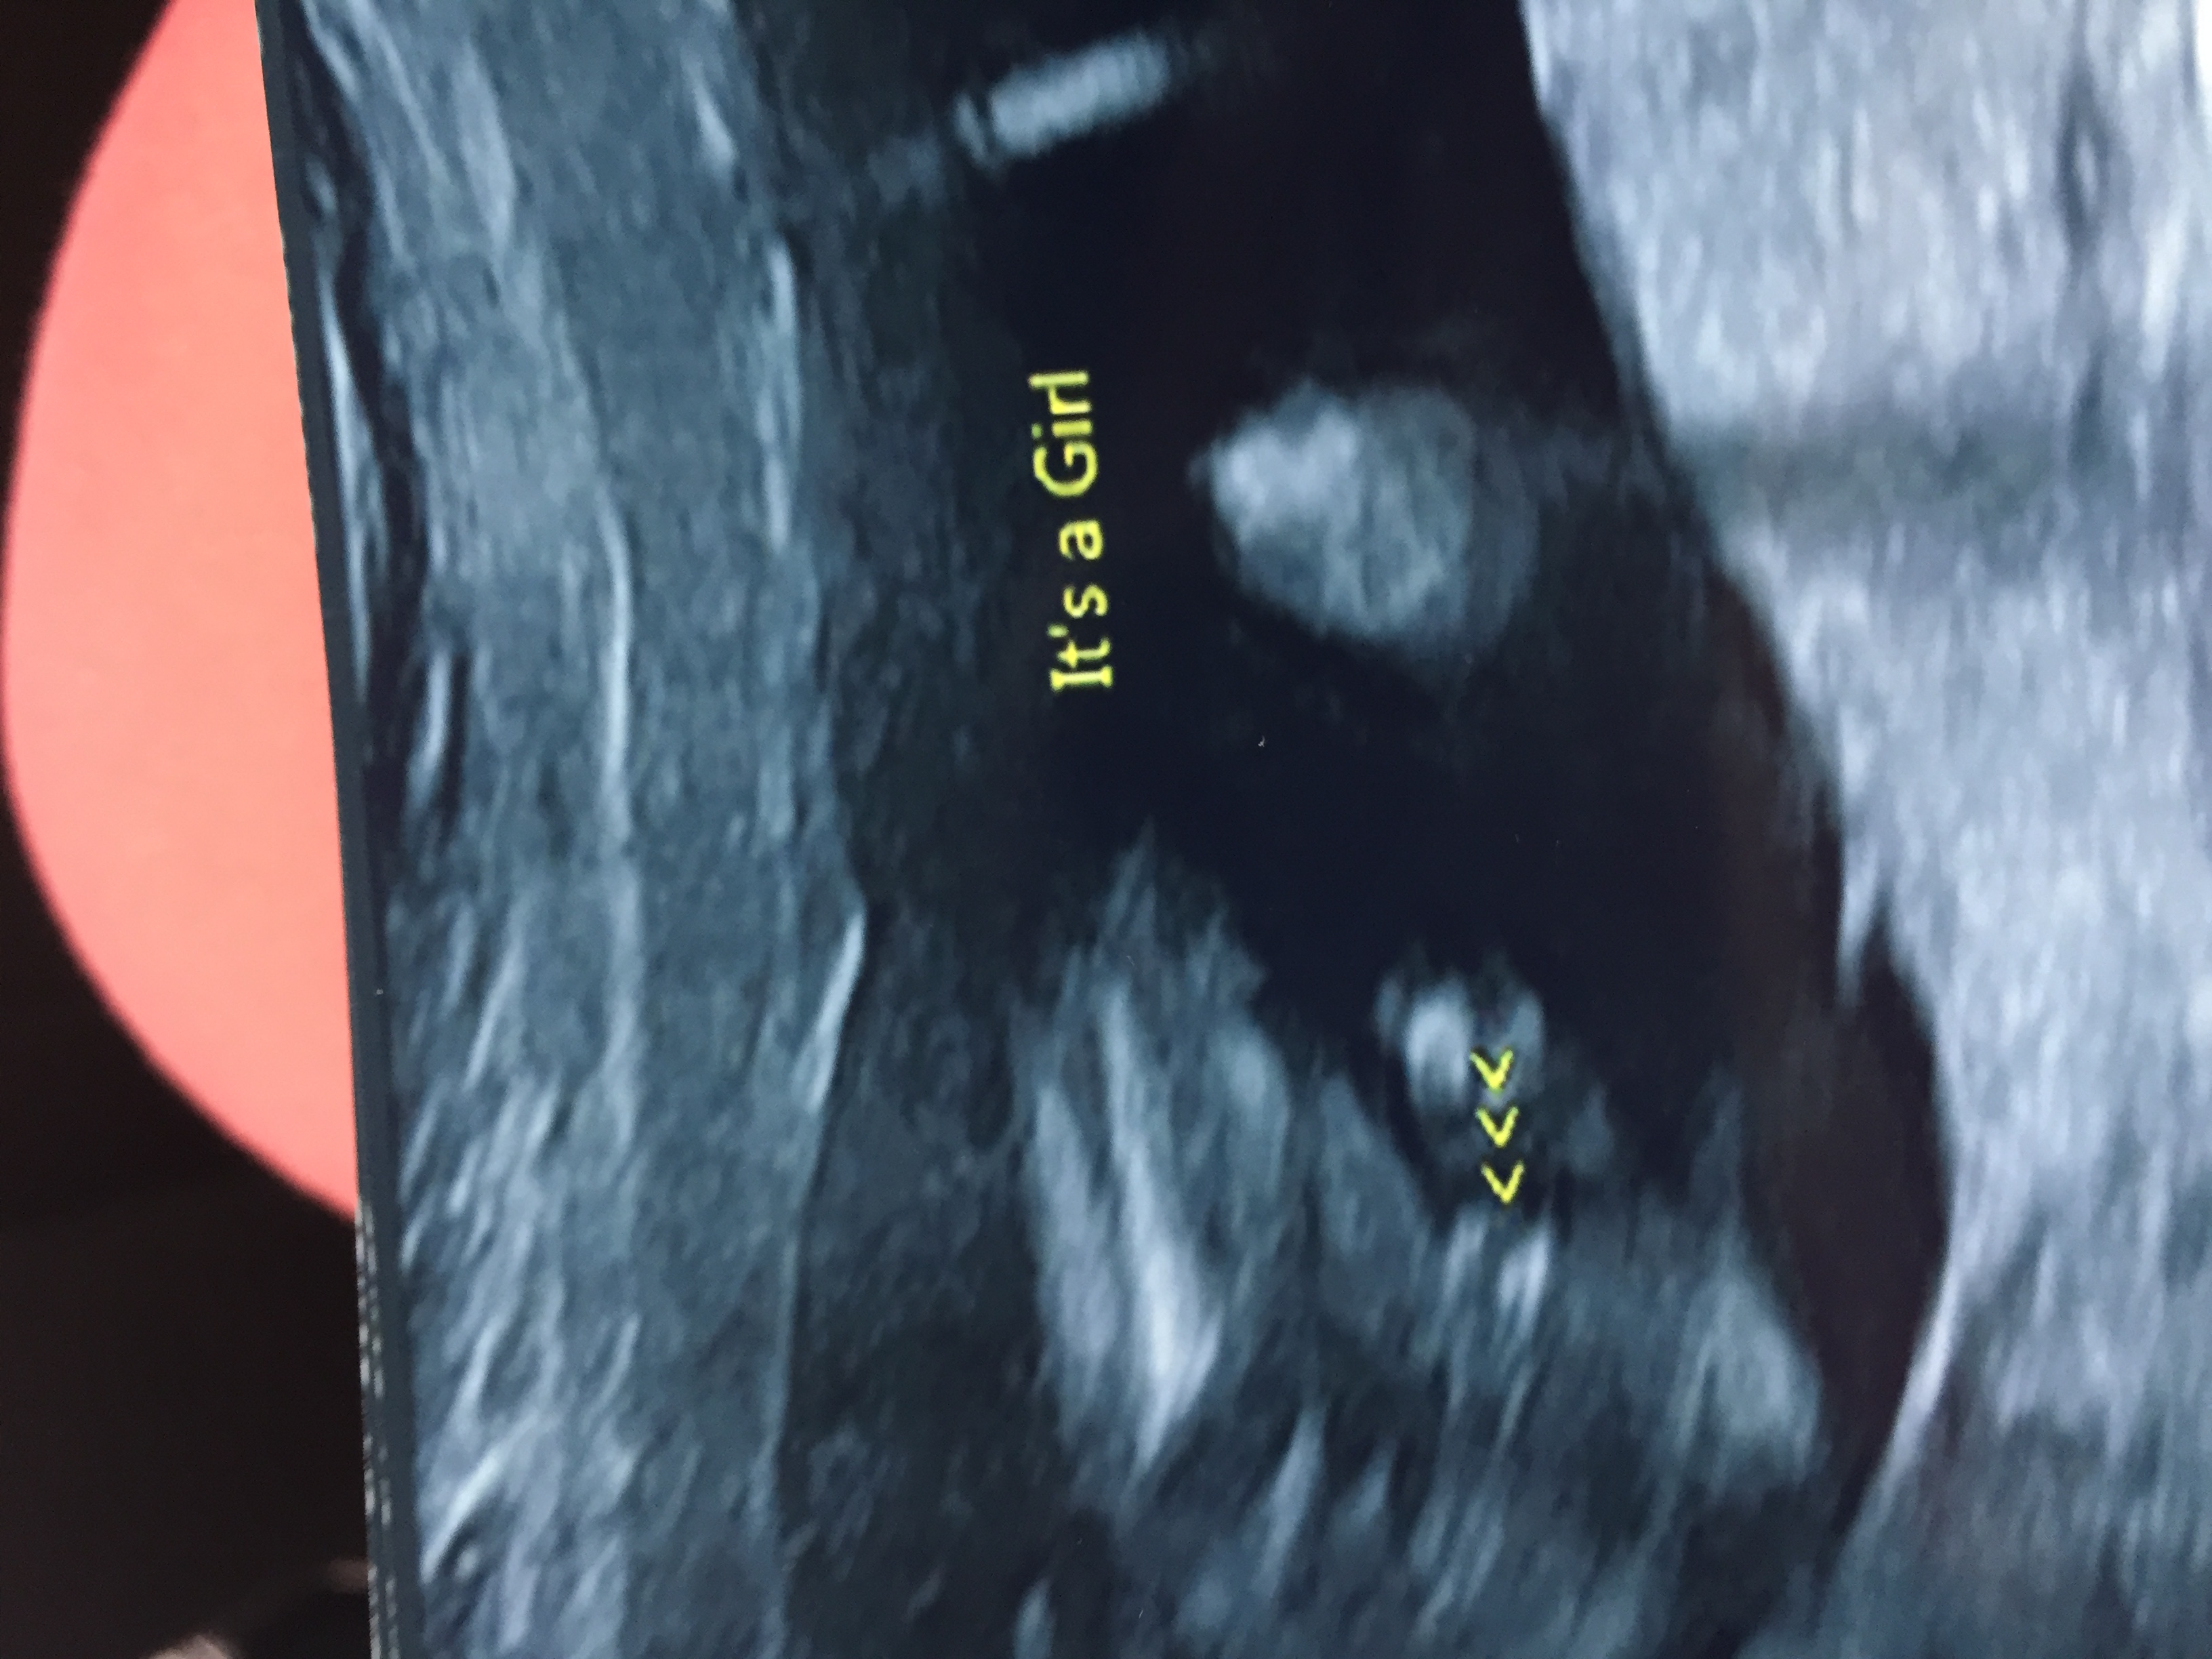

I am still in total shock......I never thought this would be me. Confirmed girl at 16+1Attachment 40150